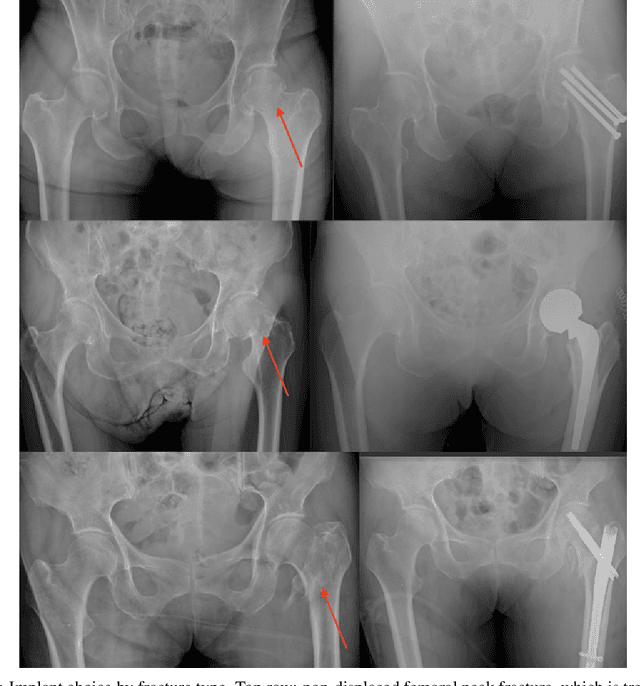

Abstract:Purpose: Hip fractures are a common cause of morbidity and mortality. Automatic identification and classification of hip fractures using deep learning may improve outcomes by reducing diagnostic errors and decreasing time to operation. Methods: Hip and pelvic radiographs from 1118 studies were reviewed and 3034 hips were labeled via bounding boxes and classified as normal, displaced femoral neck fracture, nondisplaced femoral neck fracture, intertrochanteric fracture, previous ORIF, or previous arthroplasty. A deep learning-based object detection model was trained to automate the placement of the bounding boxes. A Densely Connected Convolutional Neural Network (DenseNet) was trained on a subset of the bounding box images, and its performance evaluated on a held out test set and by comparison on a 100-image subset to two groups of human observers: fellowship-trained radiologists and orthopaedists, and senior residents in emergency medicine, radiology, and orthopaedics. Results: The binary accuracy for fracture of our model was 93.8% (95% CI, 91.3-95.8%), with sensitivity of 92.7% (95% CI, 88.7-95.6%), and specificity 95.0% (95% CI, 91.5-97.3%). Multiclass classification accuracy was 90.4% (95% CI, 87.4-92.9%). When compared to human observers, our model achieved at least expert-level classification under all conditions. Additionally, when the model was used as an aid, human performance improved, with aided resident performance approximating unaided fellowship-trained expert performance. Conclusions: Our deep learning model identified and classified hip fractures with at least expert-level accuracy, and when used as an aid improved human performance, with aided resident performance approximating that of unaided fellowship-trained attendings.